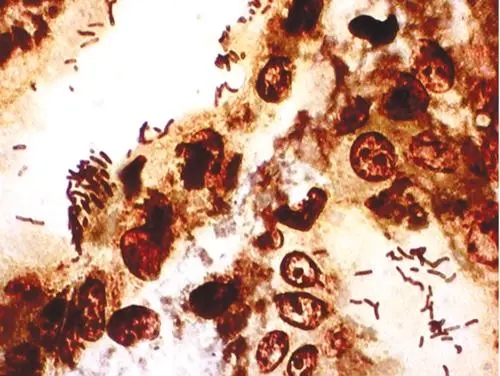

酵母菌